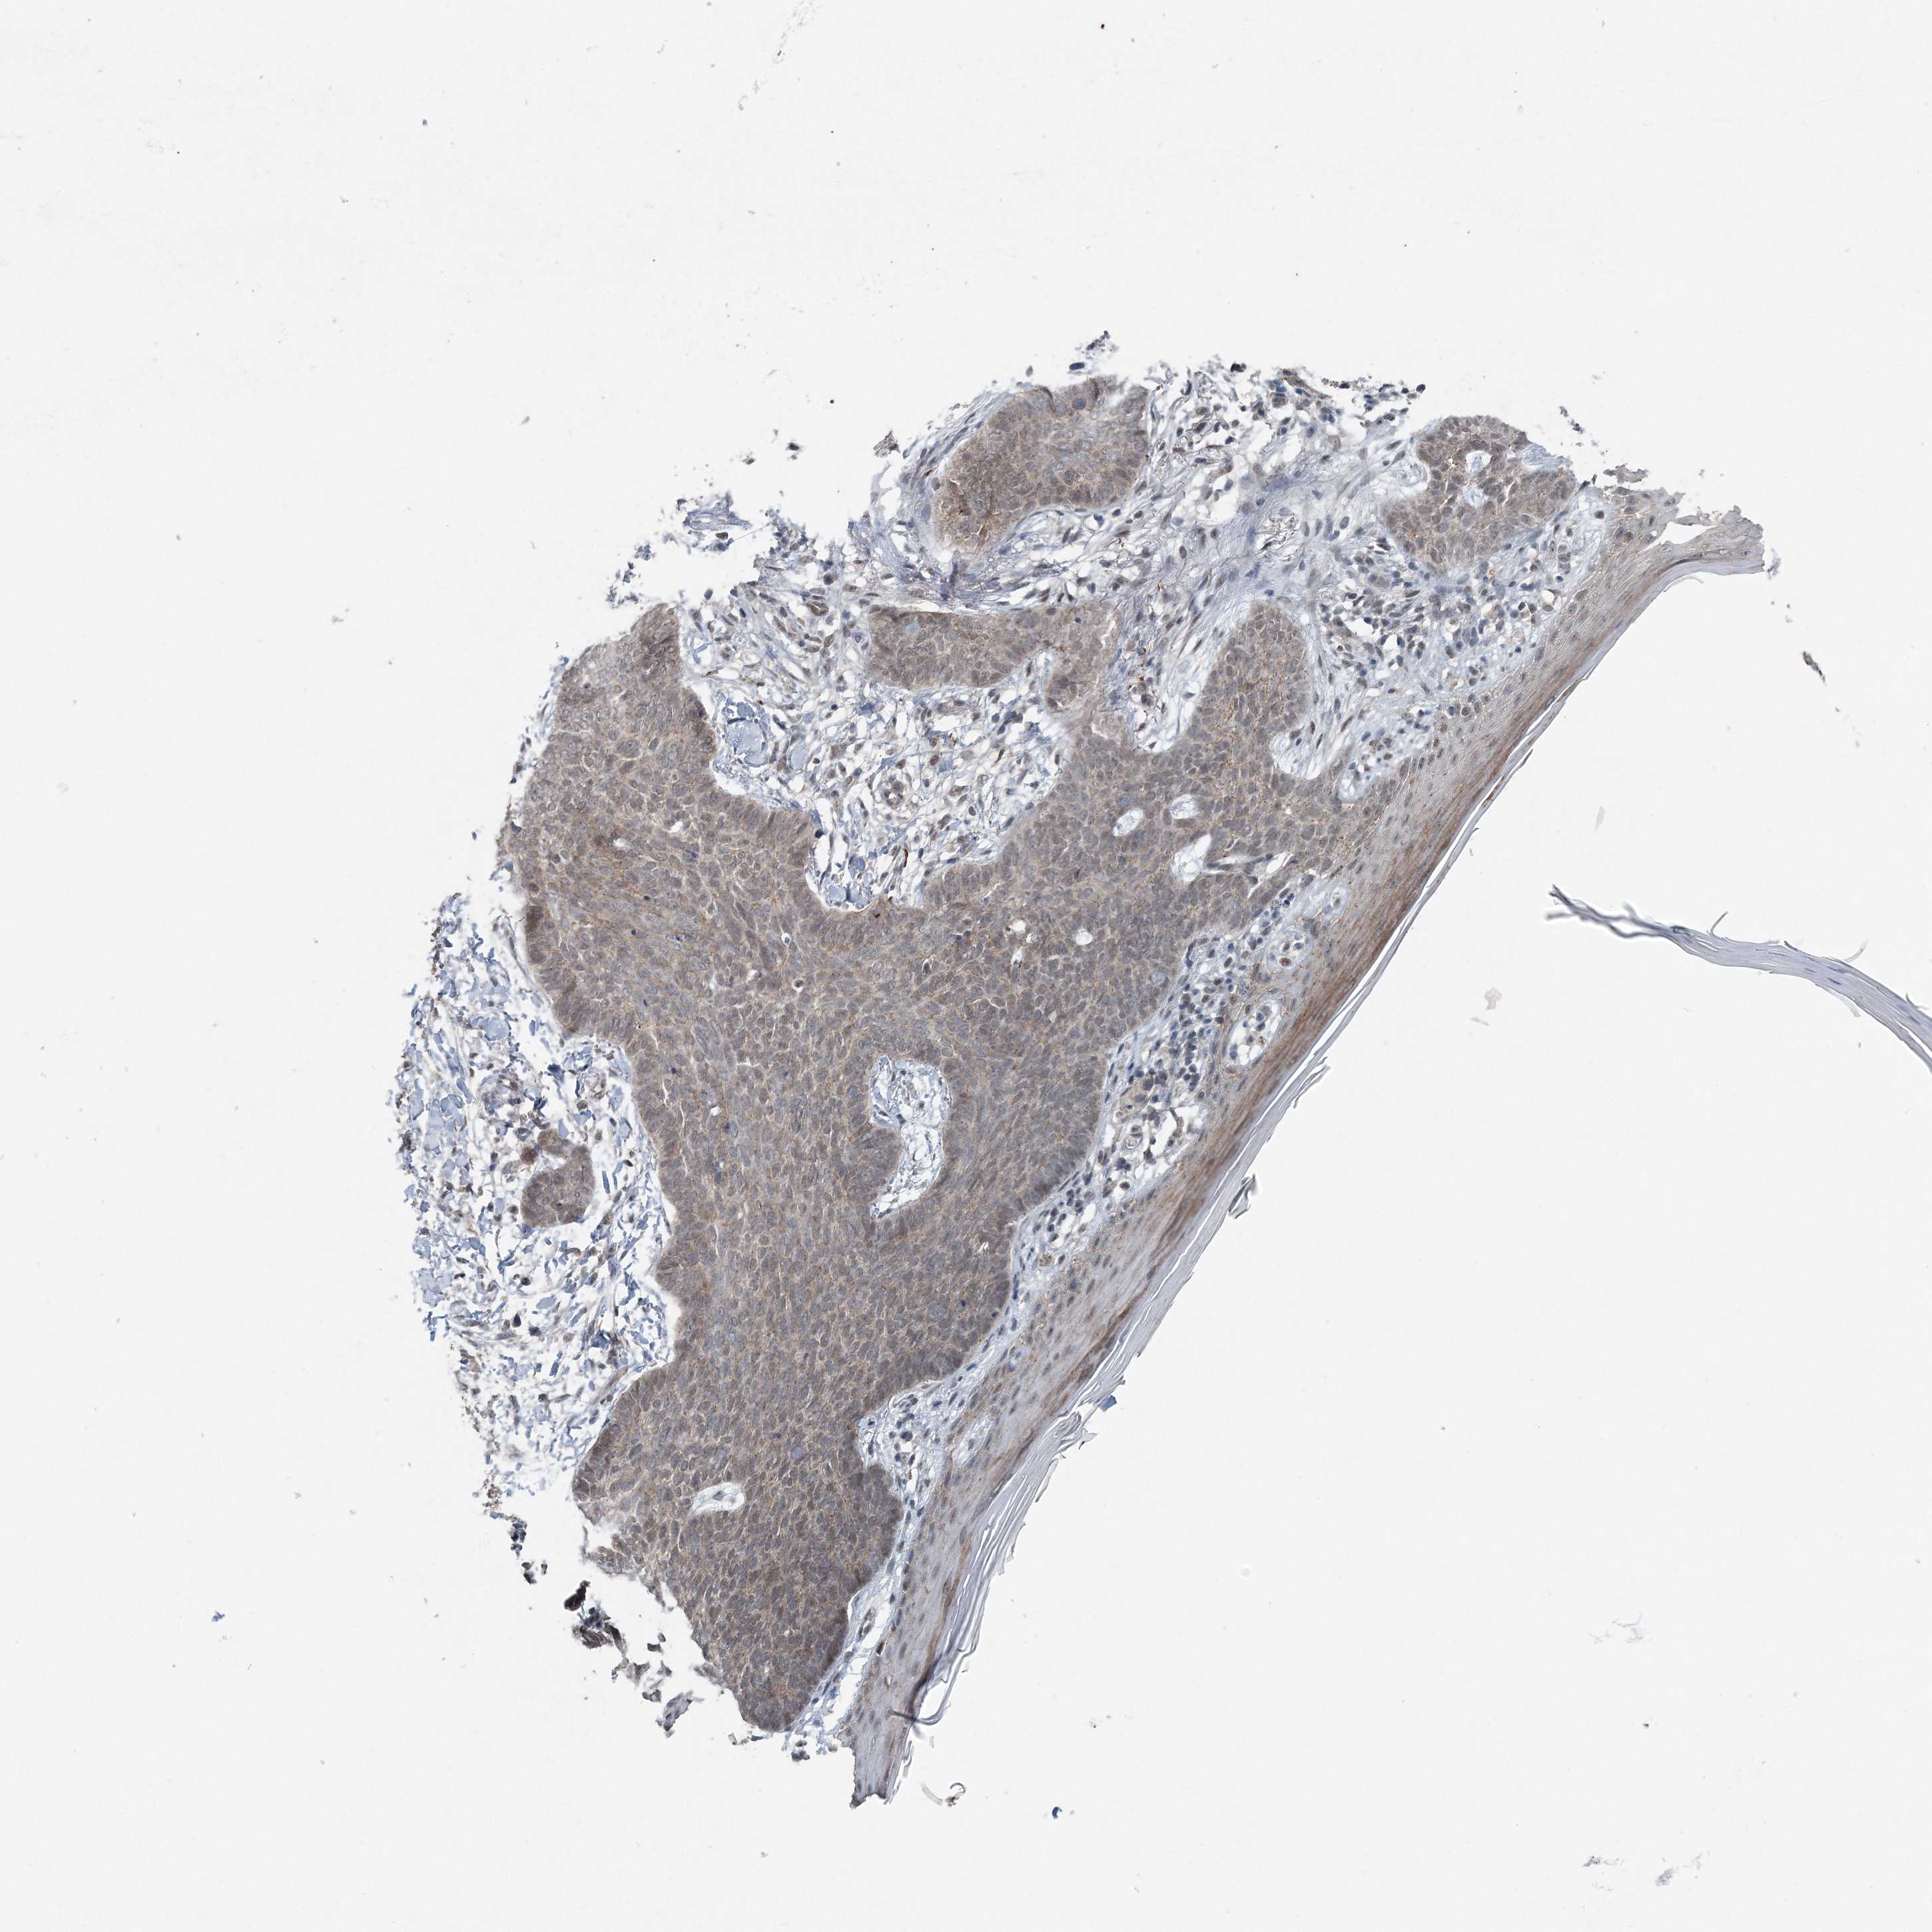

SKIN CANCER - Protein expressioni

A mouse-over function shows sample information and annotation data. Click on an image to view it in a full screen mode. Samples can be filtered based on level of antibody staining by selecting one or several of the following categories: high, medium, low and not detected. The assay and annotation is described here.

Antibody stainingi

Antibody staining in the annotated cell types in the current human tissue is reported as not detected, low, medium, or high, based on conventional immunohistochemistry profiling in selected tissues. This score is based on the combination of the staining intensity and fraction of stained cells.

Each image is clickable and will lead to virtual microscopy that enables deeper exploration of all samples and also displays staining intensity scores, fraction scores and subcellular localization as well as patient and tissue information for each sample.

Antibody HPA035919

Antibody HPA050147

Staining

High

Medium

Low

Not detected

Intensity

Strong

Moderate

Weak

Negative

Quantity

>75%

75%-25%

<25%

None

Location

Nuclear

Cytoplasmic/membranous

Cytoplasmic/membranous,nuclear

Basal cell carcinoma

Squamous cell carcinoma, NOS

Squamous cell carcinoma, metastatic, NOS